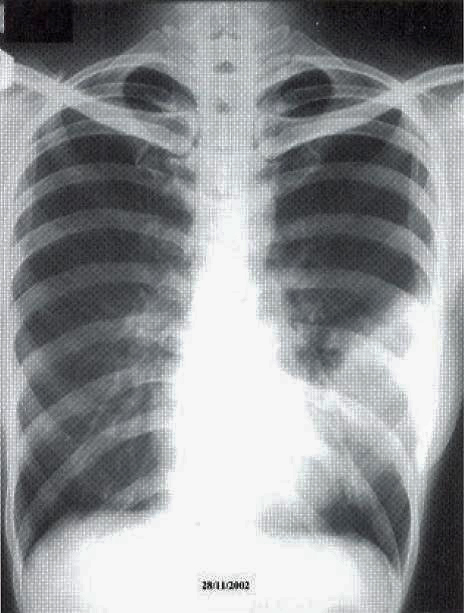

A 41-year old secretary was found having a left mid zone opacity on a routine CXR taken as part of her annual medical check-up (fig. la). This radiographic abnormality persisted after she was given a course of Azithromycin by her family physician (fig. 1b). She was a lifelong non-smoker with a past history of hyperthyroidism treated with drugs for 18 months in 1985-86 and had been euthyroid since. Two months prior to her medical check-up, she had a flu-like illness with cough and a sore throat that lasted for about a fortnight. She had been asymptomatic since apart from a slight cough occasionally. She denied any fever, weight loss, night sweat or pruritus. There was no history of taking any long-term medication or exposure to chemicals or animal pets. Clinical examination was normal and in particular, she was afebrile and not in respiratory distress. SaO2was 98% at rest whilst she was breathing room air and spirometry was normal.

Fig. 1: CXR taken at presentation (a) and 17 days later (b). Left mid zone opacity remained unchanged despite a course of Azithromycin Blood tests revealed normal CBP, ESR & routine biochemistry. Antibodies for HIV 1 & 2 were negative. Thyroid function was normal but thyroid peroxidase antibody was elevated at 81.7 IV/ml (normal <12). CT thorax showed an area of segmental consolidation in the lingular segment of left upper lobe (fig. 2a), with no abnormality detected in other parts of the lungs, mediastinum or body structures. Bronchoscopy revealed nothing abnormal and bronchial washings grew alpha streptococcus but were negative for AFB smear, M tuberculosis DNA or malignant cells. She developed a cough after the bronchoscopy and responded to a course of levofloxacin.

Fig. 1: CXR taken at presentation (a) and 17 days later (b). Left mid zone opacity remained unchanged despite a course of Azithromycin Blood tests revealed normal CBP, ESR & routine biochemistry. Antibodies for HIV 1 & 2 were negative. Thyroid function was normal but thyroid peroxidase antibody was elevated at 81.7 IV/ml (normal <12). CT thorax showed an area of segmental consolidation in the lingular segment of left upper lobe (fig. 2a), with no abnormality detected in other parts of the lungs, mediastinum or body structures. Bronchoscopy revealed nothing abnormal and bronchial washings grew alpha streptococcus but were negative for AFB smear, M tuberculosis DNA or malignant cells. She developed a cough after the bronchoscopy and responded to a course of levofloxacin.

The radiographic changes of pulmonary MALToma are non-specific. CXR and High resolution CT thorax usually show multi-focal, ill-defined nodules containing air bronchograms or focal lobar consolidation similar to what is seen in this patient. Mediastinal lymphadenopathy and pleural changes are rare. These features are similar to those seen in bronchoalveolar cell carcinoma or bronchiolitis obliterans with organizing pneumonia (3). The possibility of MALToma should be considered in patients with non-resolving pneumonia, especially if there is an absence of prominent systemic or respiratory symptoms.